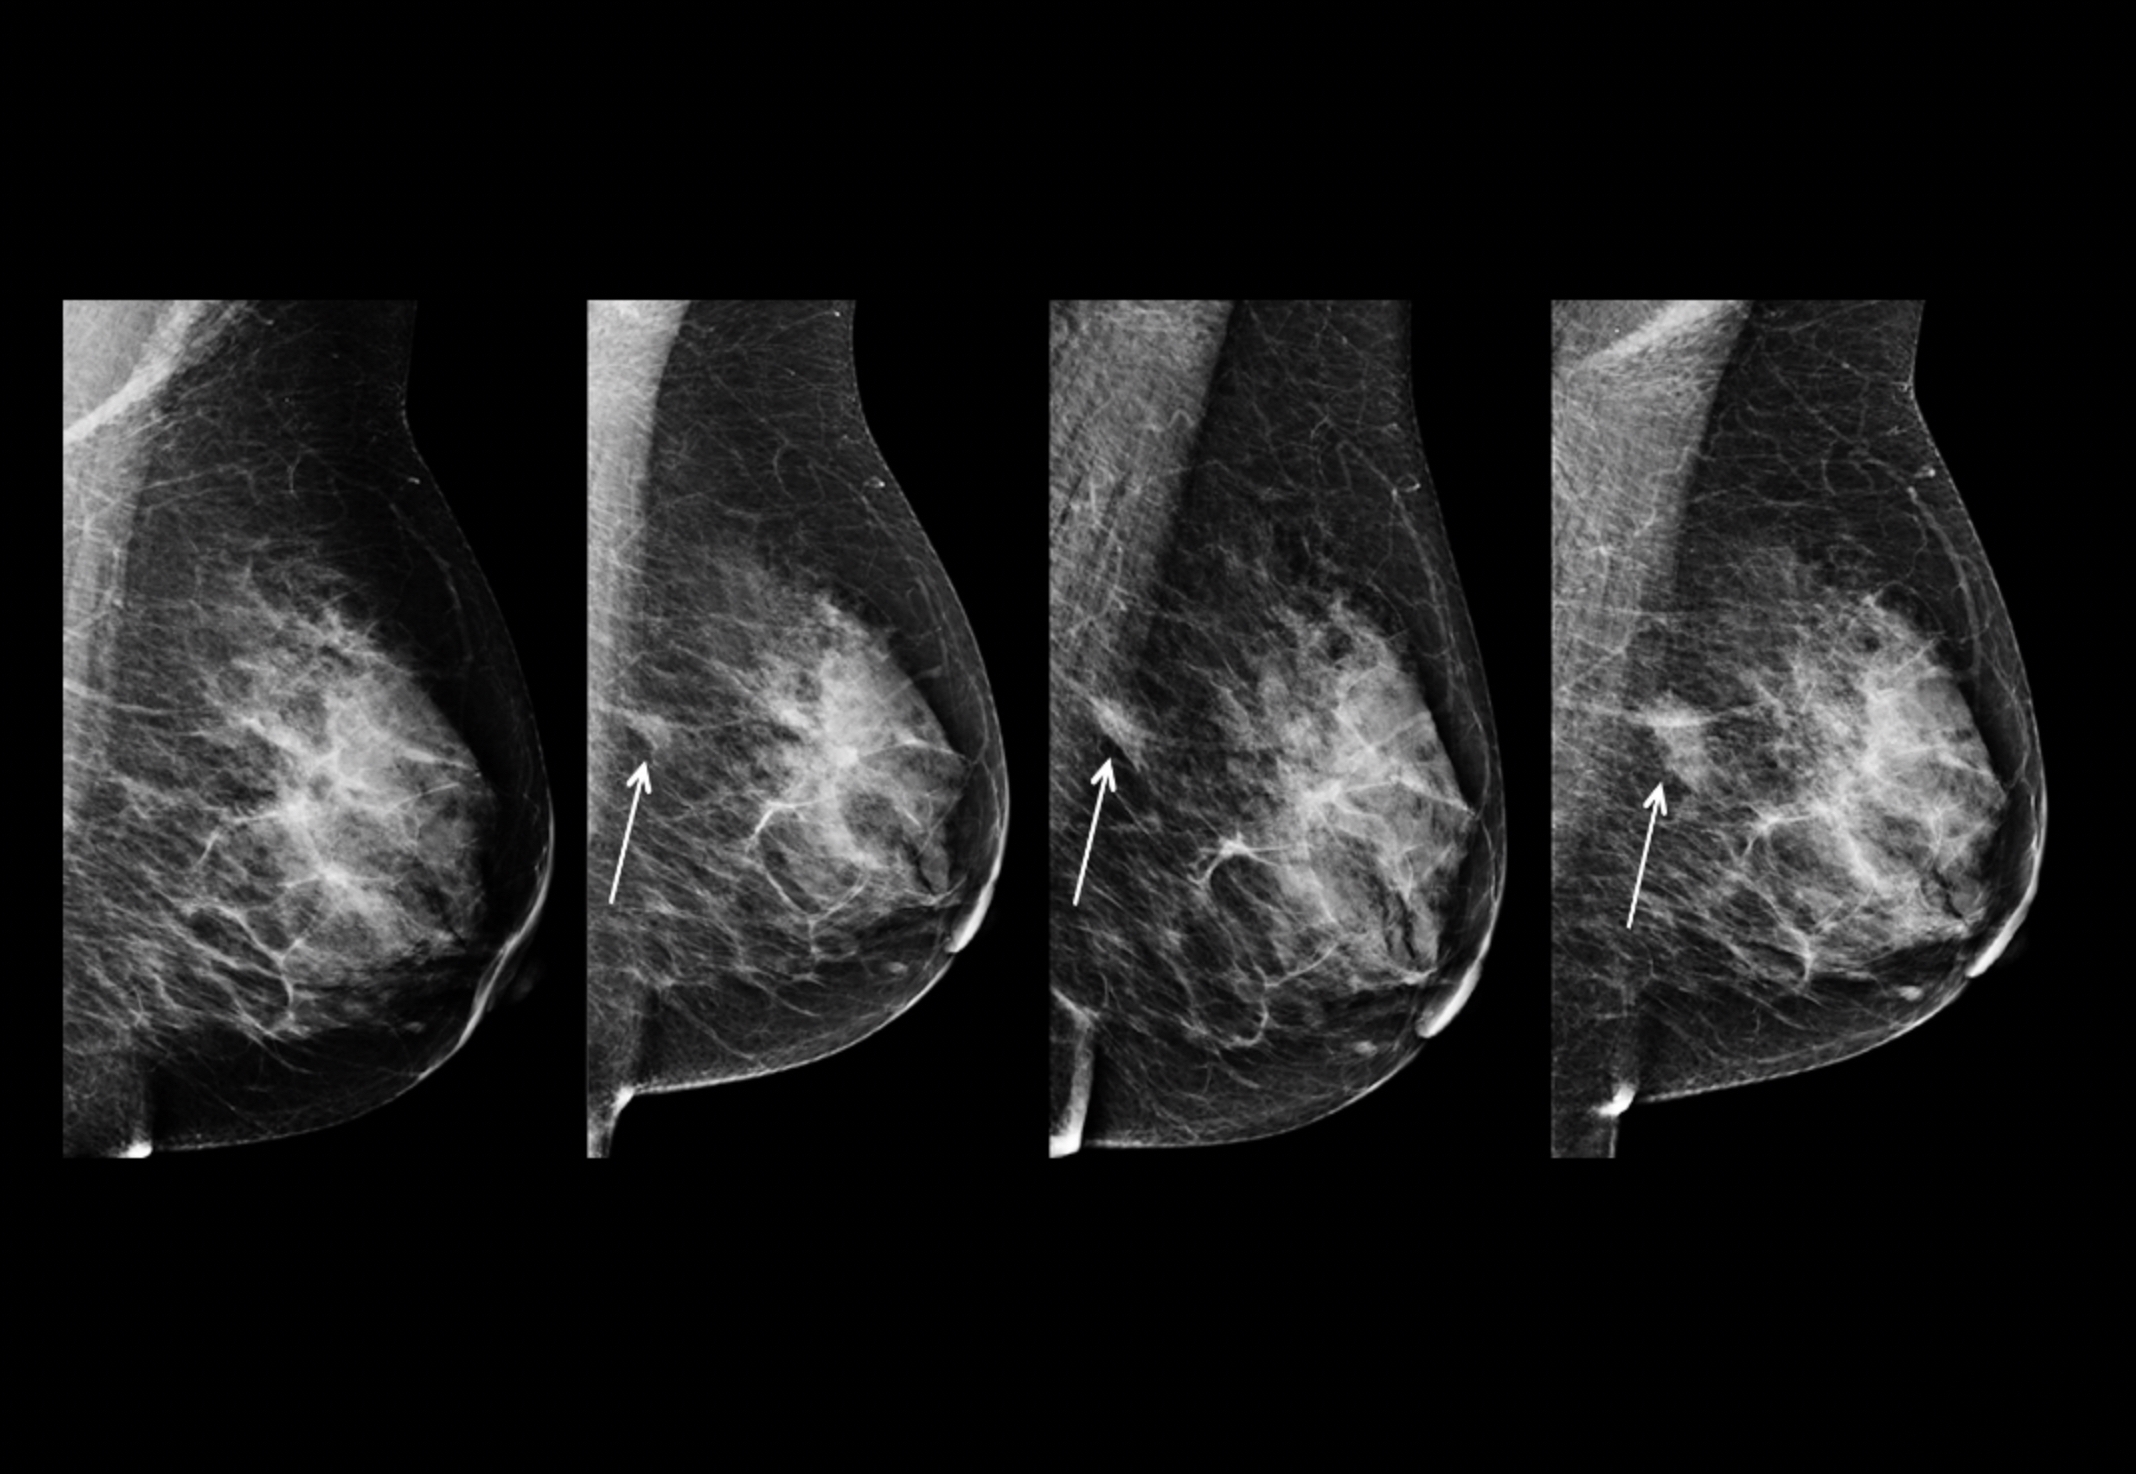

X-ray mammography is one of the most well-recognized and popular methods of breast cancer screening. It utilizes radiation to detect microcalcifications (small specks of calcium that are typically benign but can show early signs of cancer), tumor masses, and image distortions (which show contrast to highlight tumors). This radiation produces high-contrast images, with tumors and calcifications appearing as white, while other noninvasive tissue appears as a darker color, as shown in Figure 1. Radiation analyzes the shape (round and oval shapes are benign, while jagged shapes are typically malignant) and margins of a tumor to determine whether it is benign or malignant. Whenever the suspicious regions are not definitive for cancer, physicians perform biopsies, an invasive procedure. Additionally, the machines use breast compression to keep the breast in place to minimize image blurring and reduce the amount of radiation.